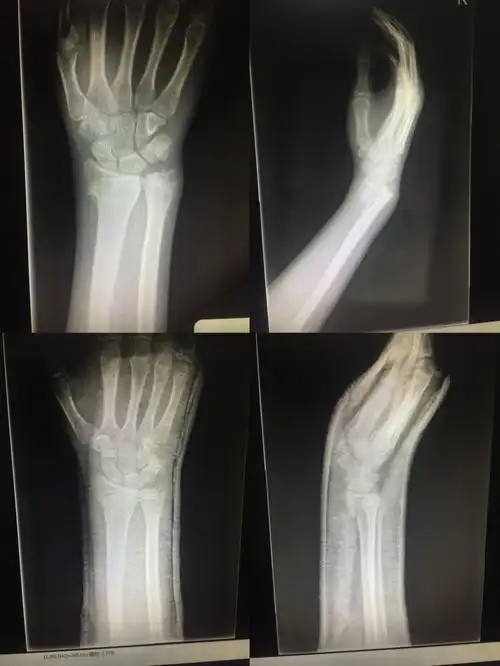

其它 南京邦德骨科医院创伤九病区 写美篇桡骨远端史密斯骨折,手法